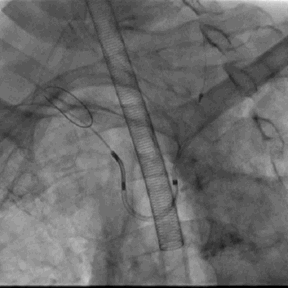

5. 超声及造影下见封堵器放置位置良好,二尖瓣及肺静脉段未见影响,测试位置固定后释放封堵器

7. 退出LAmbre左心耳封堵器系统,术程顺利,右股静脉穿刺部位予缝线缝合,右桡动脉TR BAND加压包扎,左股动予Pro-Guide内缝包扎